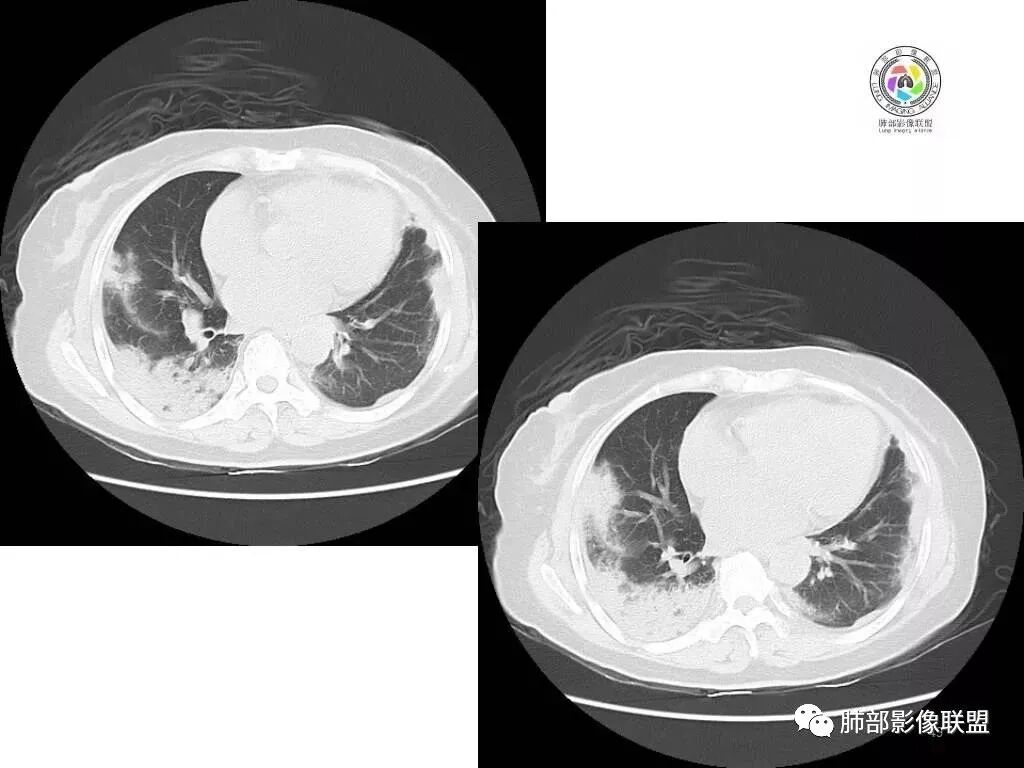

中年妇女,类风湿性关节炎病史,RF升高,感染性指标正常,双肺散在多发结节、斑片、条片灶,边缘欠清晰,大部分胸膜下分布,部分反晕,考虑RA-ⅠLD ,OP样改变

中年女性,有类风湿关节炎病史,双肺内及胸膜下见多发结节,条索状及小实变影,部分结节病灶垂直支气管血管束生长,部分结节病灶内见偏心性空洞形成,病灶收缩力弱,病灶形态多样,部分可见纤维化样改变,整体符合Op表现,结合患者病史,考虑类风湿结节,隐球菌感染不能排除。

中年女性,类风湿关节炎病史,双肺散在结节影,胸膜下分布为主,部分可见小空洞影,部分可见索条影,OP样改变,考虑类风湿结节,鉴别隐球菌

双肺散在多发结节及斑片,边缘欠清晰,胸膜下分布为主,部分内可见支气管扩张,妇女,类风湿性关节炎病史,RF升高,感染性指标正常,考虑RA-ILD,鉴别淋巴瘤。

双肺多发斑片影、结节影,胸膜下分布为主,部分沿支气管血管束分布,病灶大部分边缘平直。

双肺多发结节状及斑片状不均质磨玻璃病灶,胸膜下分布为主,边缘有收缩、凹陷,部分反晕,病灶内可见支气管扩张。中年女性,类风湿关节炎,感染指标正常。类风湿结节?隐球菌?

女,49岁,类风湿因子升高,影像双肺斑片及小结节影,胸膜下分布为主,部分病灶内支气管扩张,双侧胸膜增厚,复查病灶增多增大,考虑RA_ILD。

女性,49岁,多关节肿痛1年余。RF升高。胸部CT:双肺多发斑片影、结节影,胸膜下为主,部分沿支气管血管束分布,大小不等,部分病灶内支气管扩张,部分呈反晕,部分呈楔形宽基底贴附胸膜,复查CT进展,考虑:CTD—ILD?OP?鉴别血管炎、HP、肺梗、曲霉等。

中年女性,多关节肿痛一年,类风湿因子增高,双肺及胸膜下可见多发大小不一结节,部分呈楔形,以胸膜下分布为主,边缘平直,部分病灶分布于支气管血管束,部分可见空气支气管征、反晕征,复查病灶进展,类风湿结节?OP?

胸部CT提示双肺多发的斑片实变结节影,磨玻璃。病灶分布以双肺胸膜下为主,部分病灶以支气管血管素分布,病灶内可见支气管穿行。总体符合间质性肺疾病。

2.双肺多发片状影,胸膜下分布为主,部分沿支气管血管束分布,边界不清,实性及磨玻璃密度,趋于柔和,可见支气管进入或穿行,未见空洞、钙化及树芽等。部分病灶显示反晕。